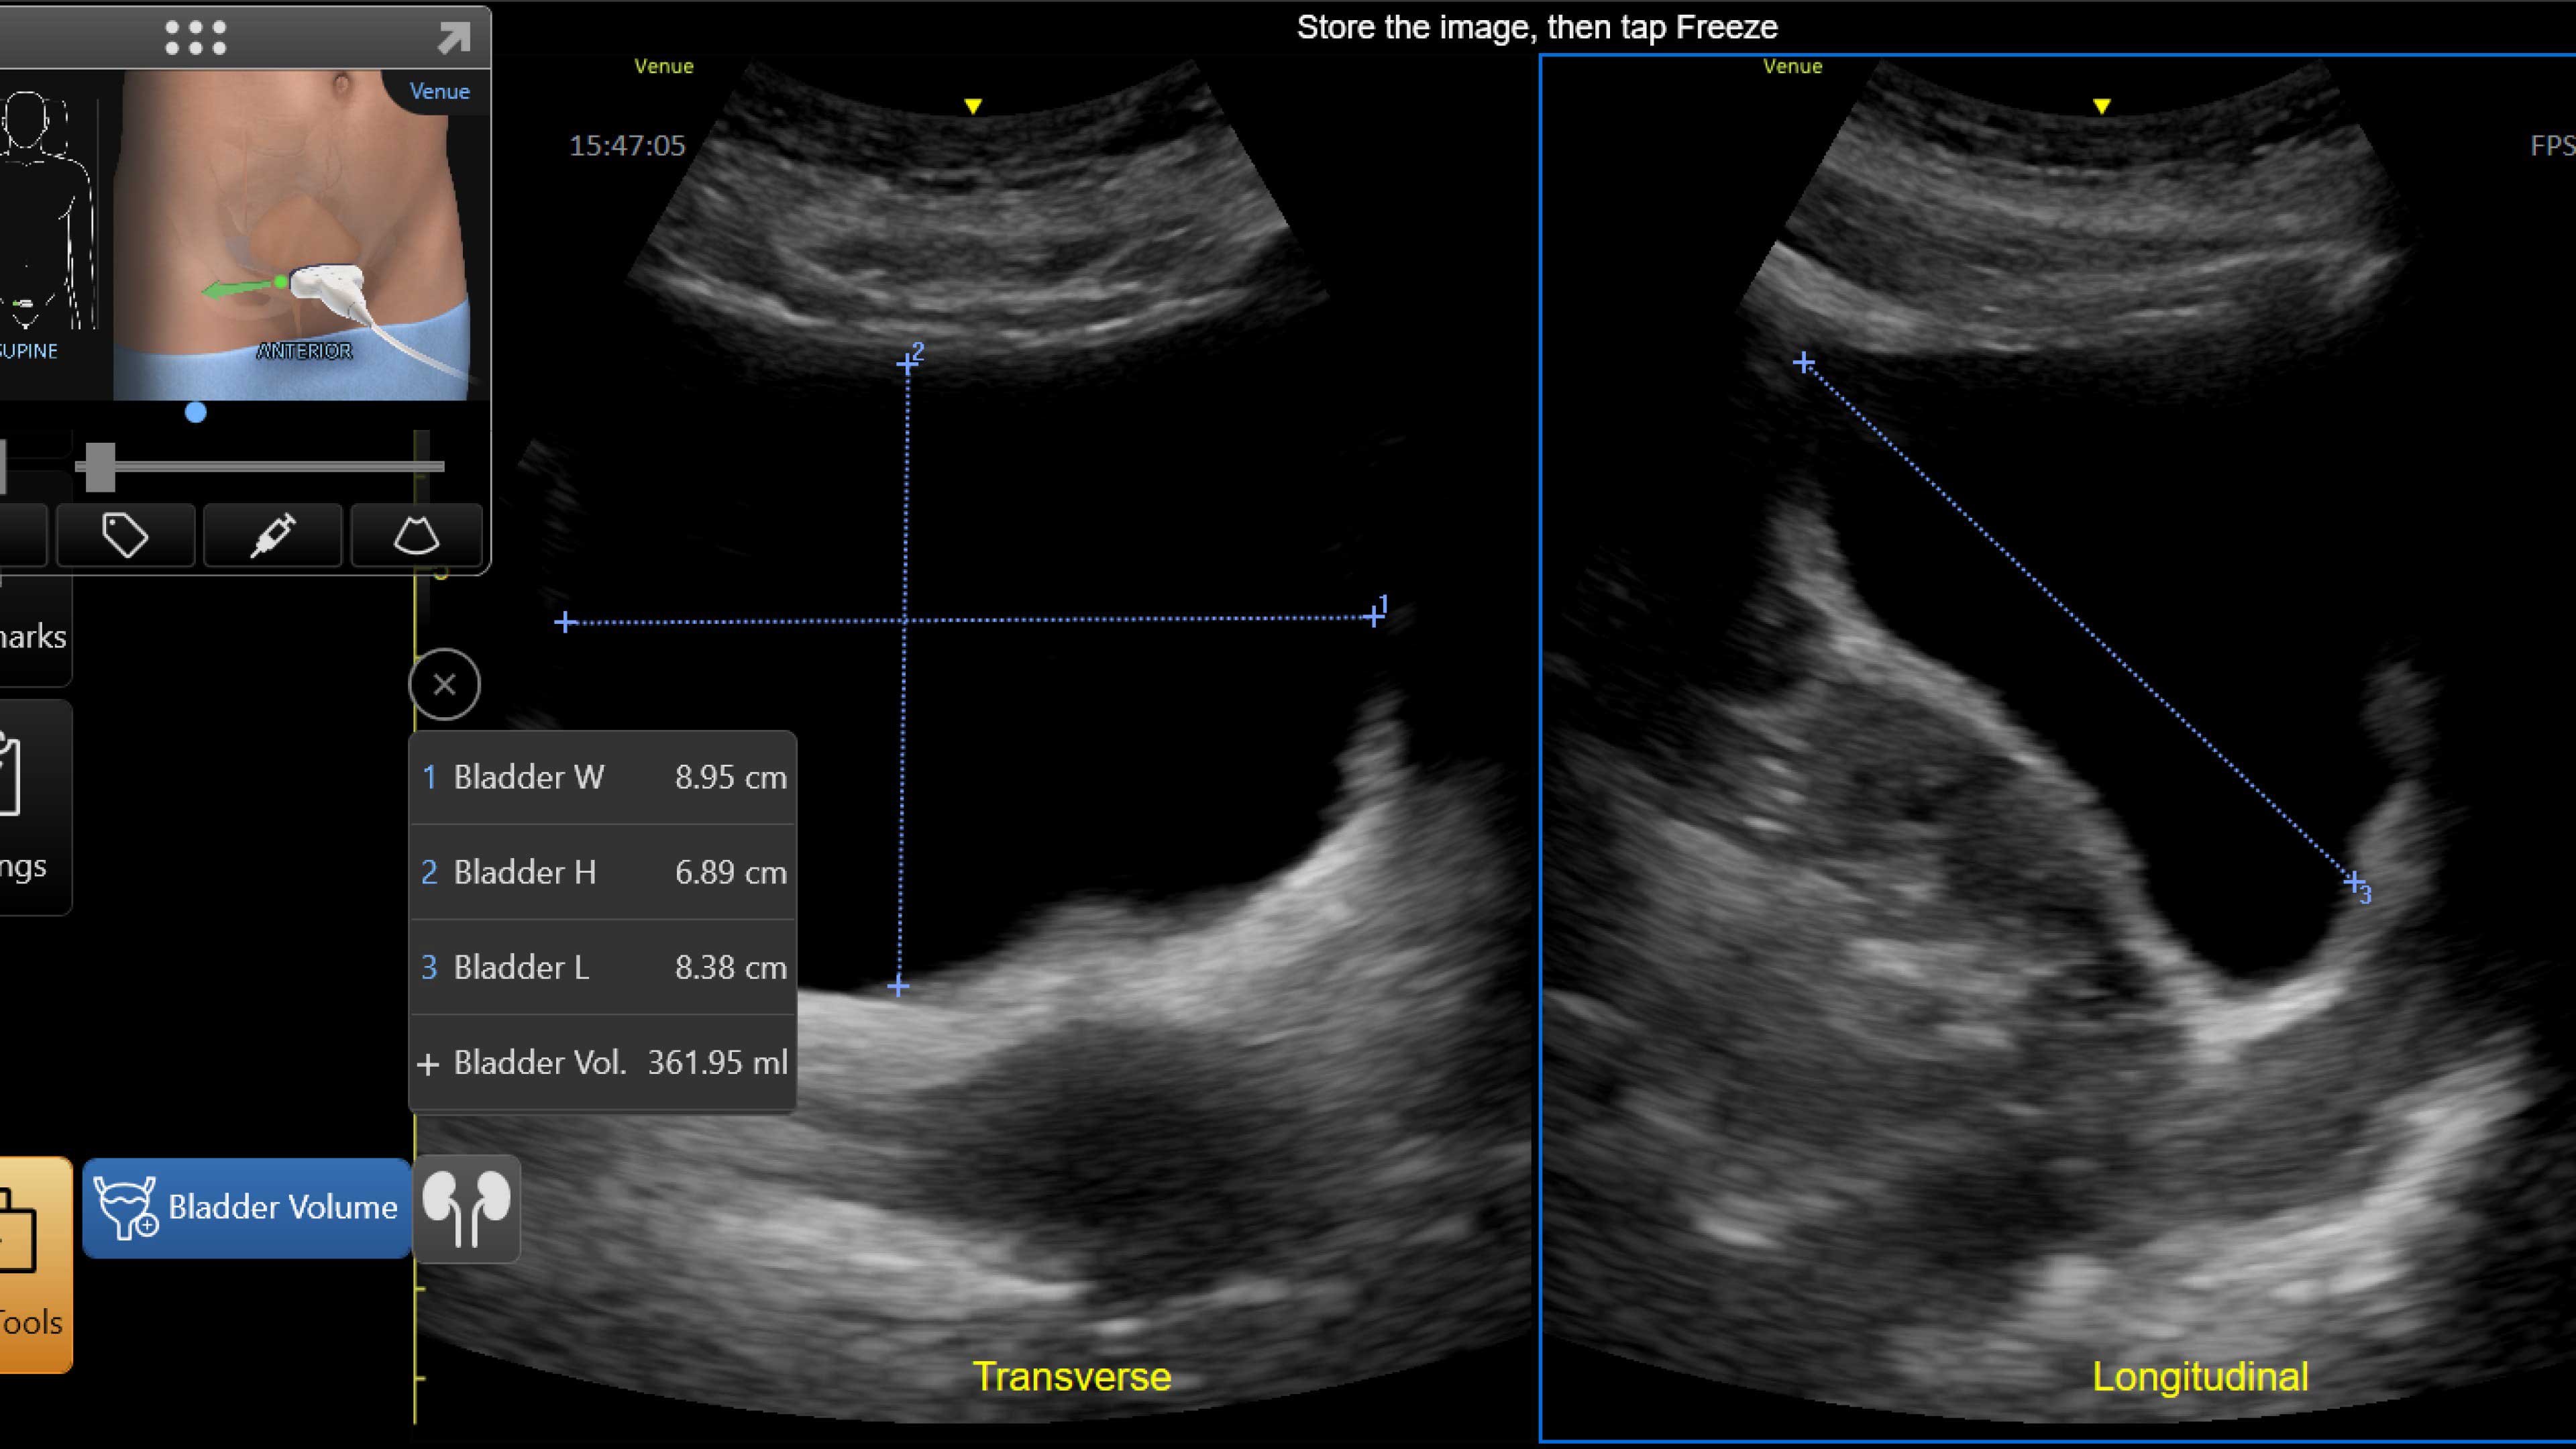

Critical care

Enables on-the-spot visual confirmation, aiding the team in decision-making and collaboration on complex cases.